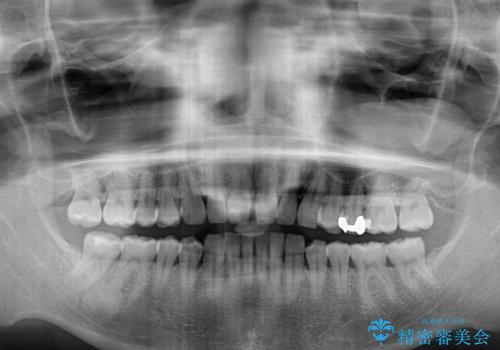

- 上顎前歯の突出感とすきっ歯を気にして来院された患者様です。

奥歯の咬み合わせを見ると、下顎に対して上顎が前方に位置していたため、補助装置により上顎歯列全体を後方に移動させ、その後インビザラインにて歯列全体を整えることとしました。